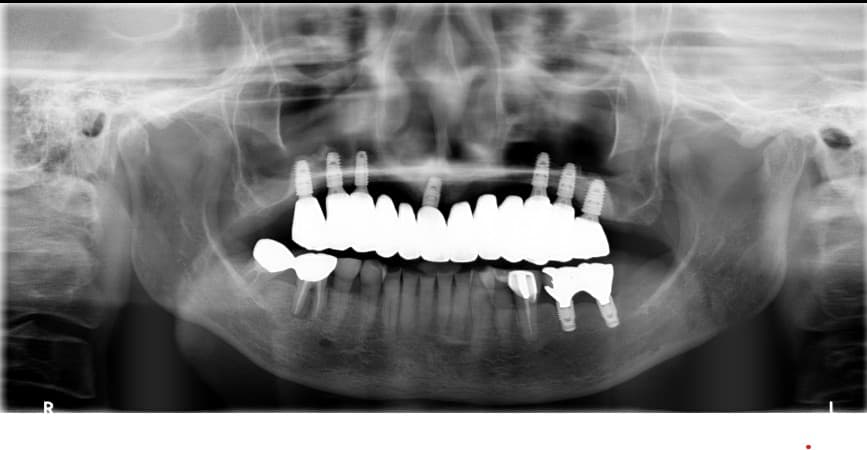

Kim●● · 60 yoshdan oshgan erkak

Yuqori jag to'liq implant

After ✨

Lee●● · 60 yoshdan oshgan ayol

Park●● · 70 yoshdan oshgan erkak

Pastki jag to'liq implant